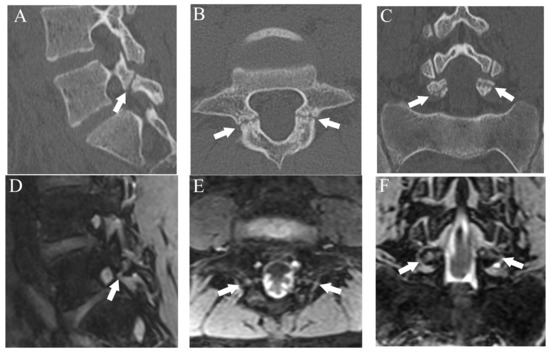

Figure 1.

Representative images of grade 1 fracture. The right pars interarticularis of L3 from a 14-year-old male. (A) Oblique-sagittal CT image showing faint attenuation in the cortex (arrow). (B) The faint attenuation corresponds to slight hyperintensity in the cortex on an oblique-sagittal DESS image (arrow). The window of the image was adjusted to enhance the faint finding. Note the BME in the pedicle (arrowhead). (C) Sagittal STIR image shows BME in the right pedicle of L3 (arrowhead).

After more than a 2-week interval from creating standard references, two readers independently analyzed fractures on T1WI and DESS using the same grading system as used in CT. On MRI, bone resorption (grade 1) can be detected as slight hyperintensity within cortical bone which normally shows homogeneous hypointensity (Figure 1). The fracture line on MRI is delineated as linear hypointensity on T1WI and linear hyperintensity on DESS (Figure 2 and Figure 3). DESS was also used to evaluate the BME binary. Similar to STIR, if there is a high signal at pars interarticularis on DESS, it is considered positive for BME. Consensus results for T1WI, DESS for fracture and DESS for BME were created for statistical analysis.